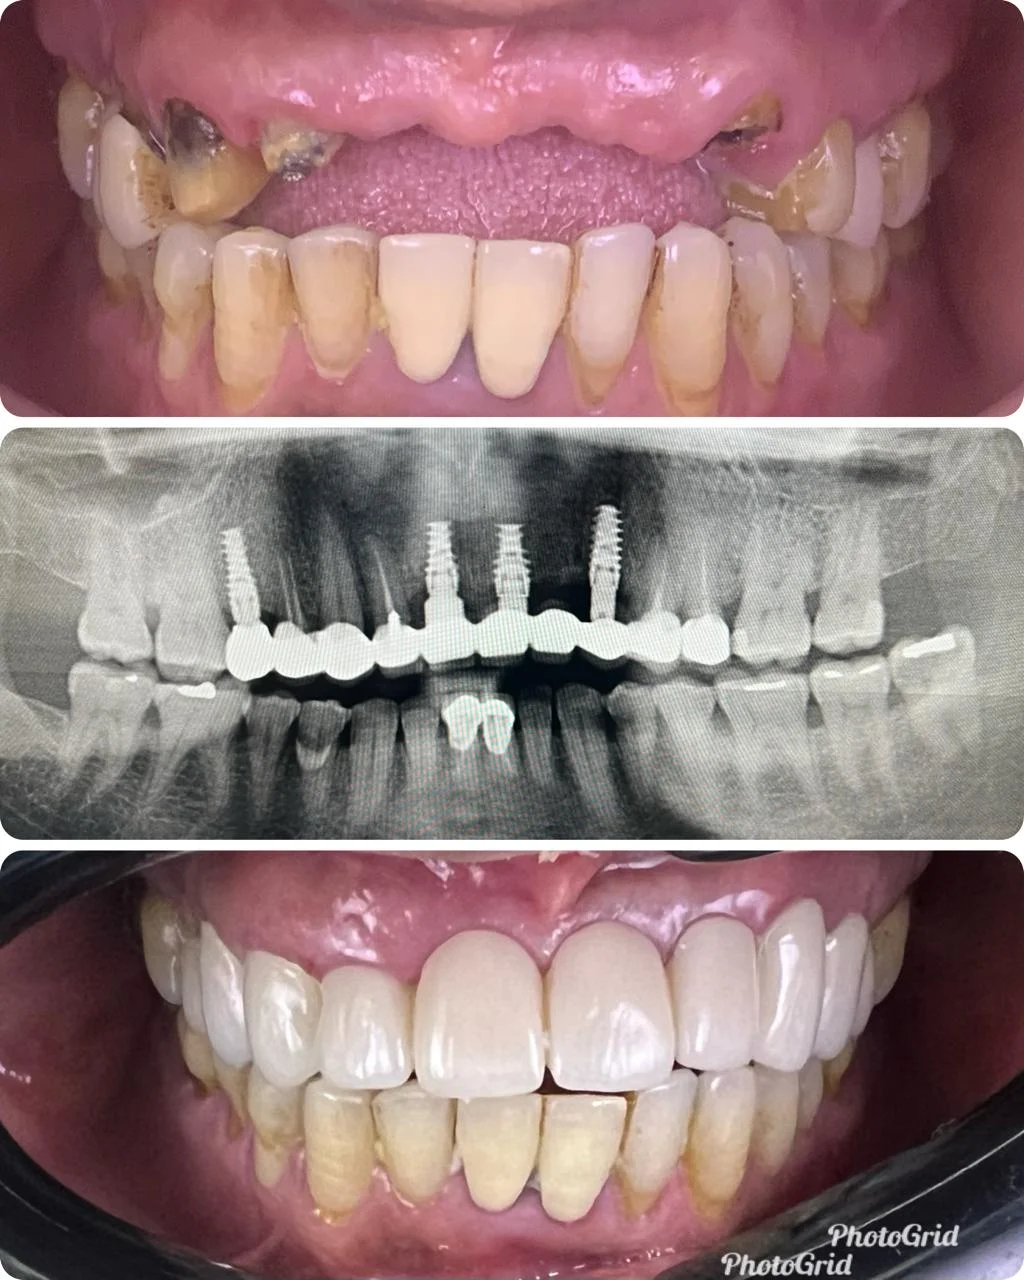

Showing Our Expertise In Dental Implantology